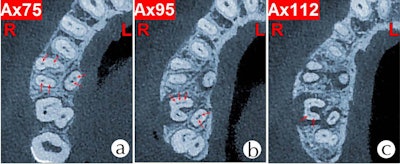

Fortunately, CBCT scans effectively analyze root canal anatomy by visualizing multiple orientations in very thin slices without disturbing the overlapping structures, the authors wrote. The combined use of a dental operating microscope with CBCT aids identification of and work on root canals in the upper molars.

CBCT scans gave a better view of the teeth and verified the findings. Clinicians prepared six canals in tooth #16 with two in the mesiobuccal root, two in the distobuccal root, and two in the palatal root. They also prepared seven canals in tooth #17: three in the mesiobuccal root, two in the distobuccal root, and two in the palatal root, the authors noted.